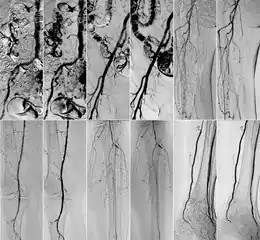

Comparison of kinetic images(KIN) and DSA images in abdominal (top row) and iliac regions (bottom row).

DSA (left) and DVA (KIN, right) image pairs, which were created by administering iodinated contrast agent. From top to bottom: abdominal, iliac, femoral, popliteal and crural regions.

In 2018 Gyánó M. et al. compared the quality of DVA and DSA (digital subtraction angiography) images in a prospective observational crossover study, which involved the analysis of 232 image pairs of 42 patients undergoing lower limb x-ray angiography (performed by using iodinated contrast agent) between February and June 2017. Methods included the measurement of SNR (signal-to-noise ratio) and visual quality comparison.[1]

Although other factors like spatial resolution, sharpness, and object size may contribute to image quality and object perceptibility, noise places a fundamental limitation on the ability to recognize structures on low-contrast images and that was the main reason why the SNR measurement method was chosen. The results showed 2-3 times higher SNR values in the case of DVA images compared to traditionally used DSA images, which has indicated that DVA has the potential to improve the ability to view blood vessels, since a higher SNR value indicates lower noise levels.

Qualitative comparison has been performed by three vascular surgeons and three interventional radiologists, with about 17 years of experience on the average. In an online visual questionnaire, which showed DVA and DSA image pairs of the same anatomical regions, raters were asked to choose the image which they found to be more useful for making the diagnosis. Overall, the raters judged the kinetic images better in 69% of all images. Regarding different anatomical regions, the raters agreed that the DVA was significantly better for talocrural and popliteal regions.